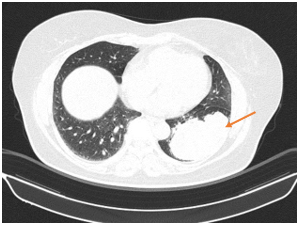

Hình 2. Thuỳ dưới phổi trái có khối đặc lớn, bờ thuỳ múi không đều, kích thước ~ 89x54,5mm xâm lấn màng phổi lân cận

Hình 3. Đỉnh phổi phải có khối bờ thuỳ múi tua gai kích thước 35x36mm, theo dõi xâm lấn màng phổi thành lân cận.